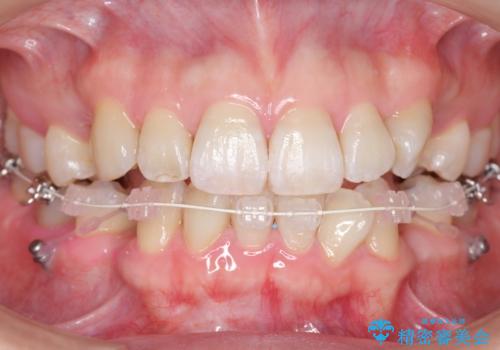

- ハーフリンガル

矯正治療で右下を抜歯し、スペースを天然の歯でつめる矯正治療を行いました。

上顎前歯も唇側傾斜しておらず、もともと叢生が多くない状態で上下左右を抜歯した上、リンガルで治療を行なったため、多少治療期間がかかりました。